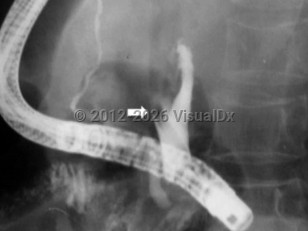

AscariasisAscariasis